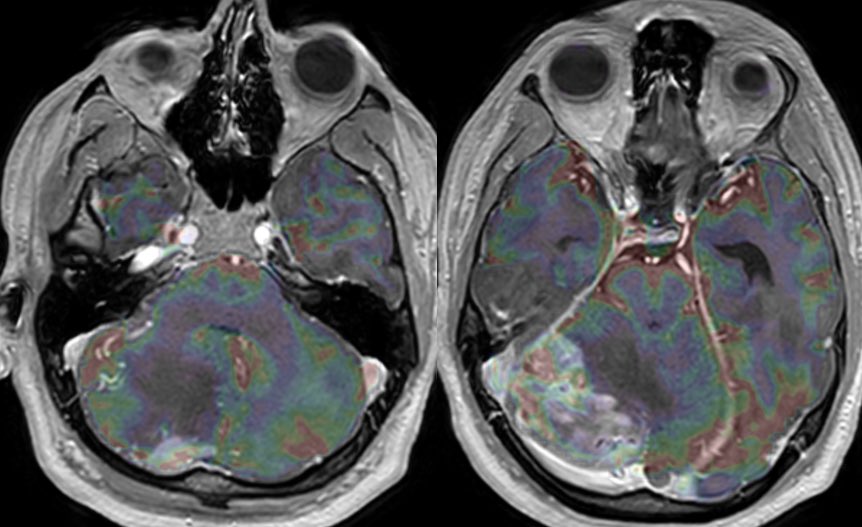

MRI: Enlarged or swollen right cerebellar hemisphere

T1: Hypointense with curvilinear high signal (slow flow in vessels)

T2: multiple tortuous flow voids and extensive edema but PRESERVED FOLIA

T1C+: bizarre somewhat geographic enhancement of the parenchyma and leptomeninges

MR perfusion shows increased CBV within the enhancing components